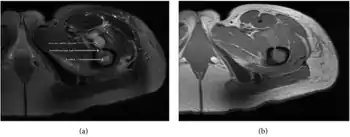

| a,b) MRI showing the Brodie's abscess in the left proximal femur | |

Fat saturated STIR (short tau inversion recovery) image showing hyperintense edema in the calf musculature, marrow edema, and subperiosteal pus. The intramedullary abscess cavity is hyperintense as well.

Coronal fat suppressed STIR image showing, bone marrow and subcutaneous edema as well as subperiosteal edema. The thin hypointense rim surrounding the intramedullary collection represents the reactive interface between the abscess and the body's attempt to wall it off.

Axial T1-weighted MRI pre-contrast enhancement showing that the intramedullary collection is T1-hyperintense suggesting proteinaceous viscous fluid consistent with infection.

Axial T1-weighted fat-saturated MRI image following IV gadolinium contrast demonstrating the intramedullary lytic area seen on radiography to be ring enhancing consistent with a purulent fluid collection. Extensive circumferential periosteal enhancement is noted. There is also substantial bone marrow enhancement.